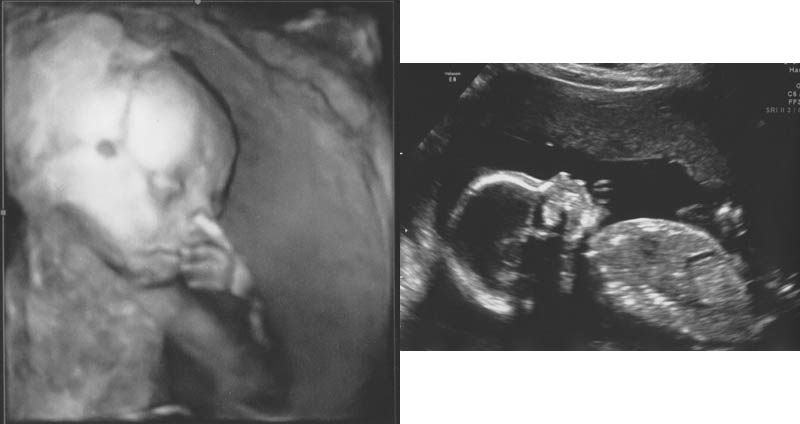

16 Weeks (3D Imaging!)